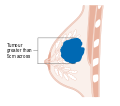

| رسم لسرطان الثدي. | |

- المرحلة: مراحل سرطان الثدي باستخدام نظام TNM يعتمد على حجم tumor (T) "الورم" سواء أكان أم لم يكن منتشراً إلى العقد nodes (N) اللمفاوية تحت الإبط، أو كان الورم metastasized (M) "منتشراً" (أي منتشر لأكثر من مكان في الجسم). حجم أكبر، انتشار عقدي، والورم الخبيث له رقم مرحلة أكبر ومآل أسوأ.

هذه المراحل الرئيسية هي:- المرحلة 0: هي حالة أو علامة ما قبل سرطانية، إما سرطان القنوات الموضعي (DCIS) أو السرطان الفصيصي الموضعي (LCIS).

- المرحلة 1–3: تكون داخل الثدي أو الغدد الليمفاوية الإقليمية.

- المرحلة 4: هو السرطان "النقيلي" الذي له مآل أقل مواتاة لانتشاره خارج الثدي والغدد الليمفاوية الإقليمية.